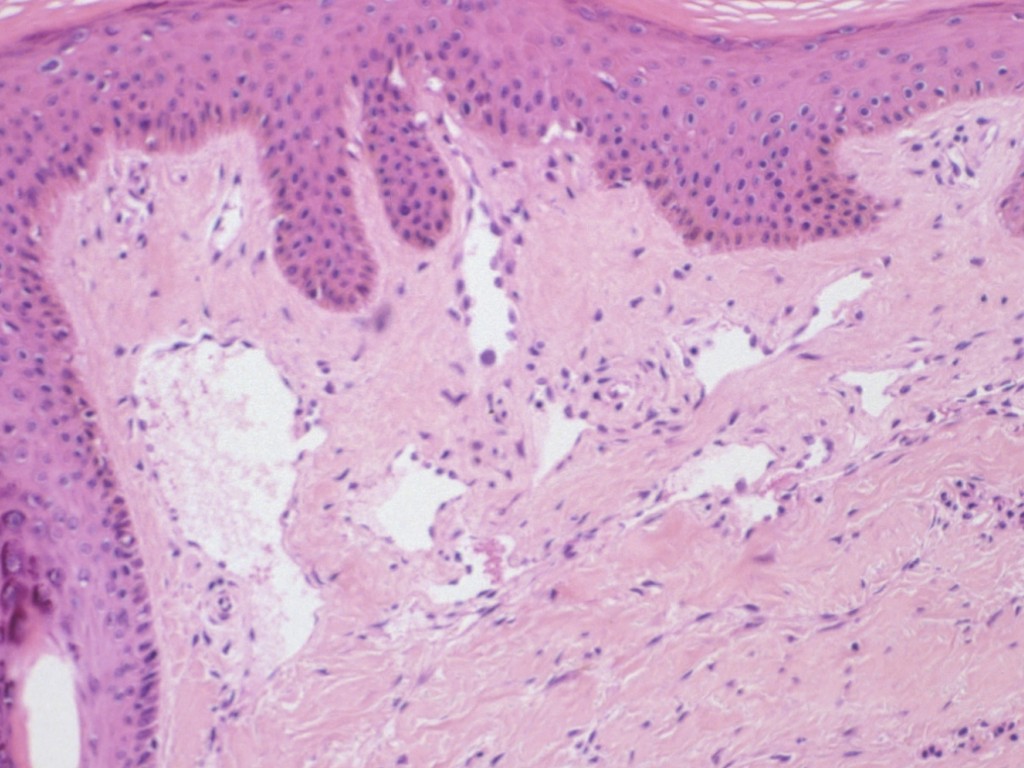

Een

hobnail hemangioma (synoniem:

targetoid

hemosiderotic hemangioma) is een goedaardige

vasculaire tumor

die er klinisch uitziet als een klein hemangioom. Histologisch wordt het gekenmerkt

door endotheel waarvan de kernen als kopspijkertjes (hobnails) uitsteken in

het lumen. De diagnose wordt meestal pas gesteld door de patholoog, op materiaal